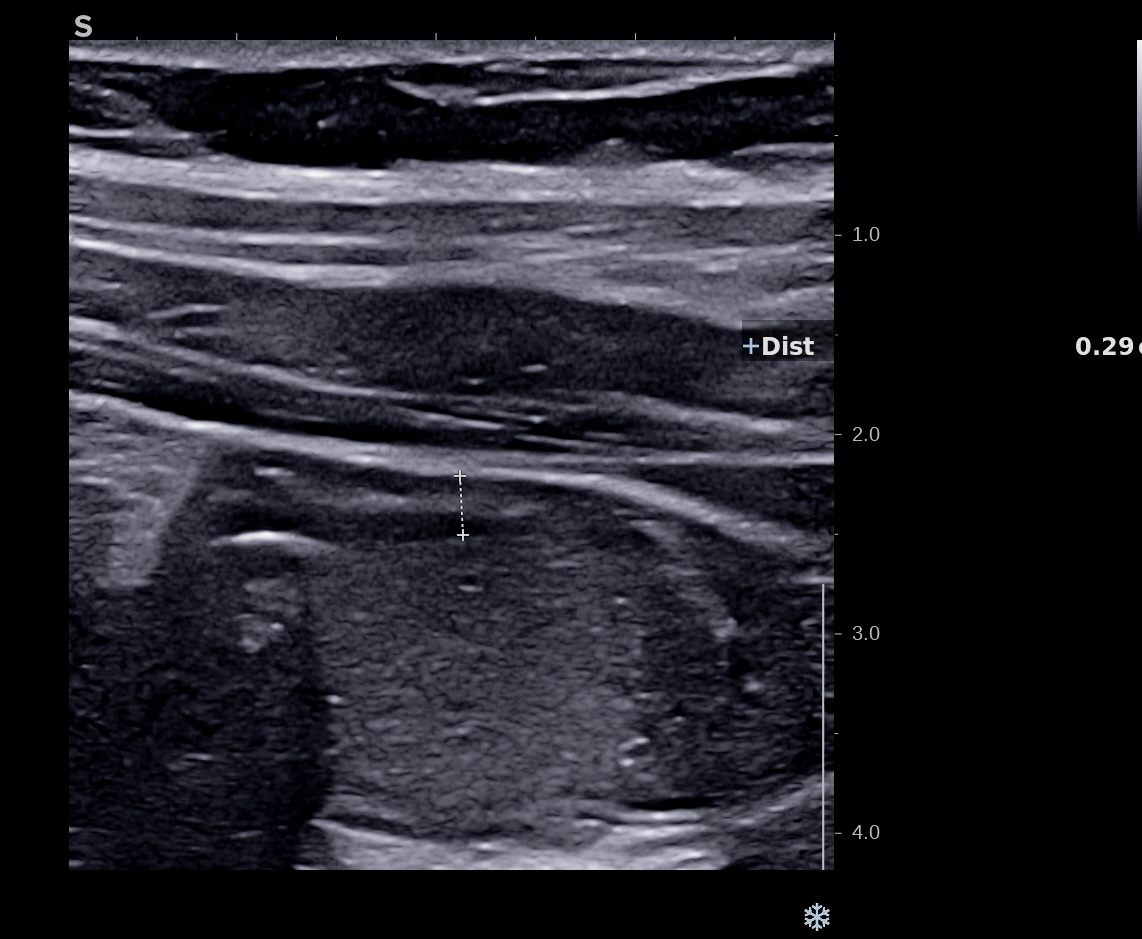

Dès J7 l’amélioration échographique de la paroi se poursuit. L’épaisseur pariétale approche la normale (3 mm) et par endroit 2,1 mm, les couches sont bien visibles, le doppler reste intense (Limberg 3) .

le score de Milan, segment le plus atteint est de (3 x1,4 +2) MUC = 6,2

la maladie reste active, mais la réponse est impressionnante et se poursuit.

La paroi est redevenue strictement normale, rien ne permet de la différentier d’un colon sain.

L’épaisseur pariétale est de 1,8 mm, structure en couche totalement rétablie, le Doppler est négatif, Limberg 0.

On retrouve les haustrations coliques normales.

Le score de Milan est de (1,8 x1,4+0) MUC = 2,52